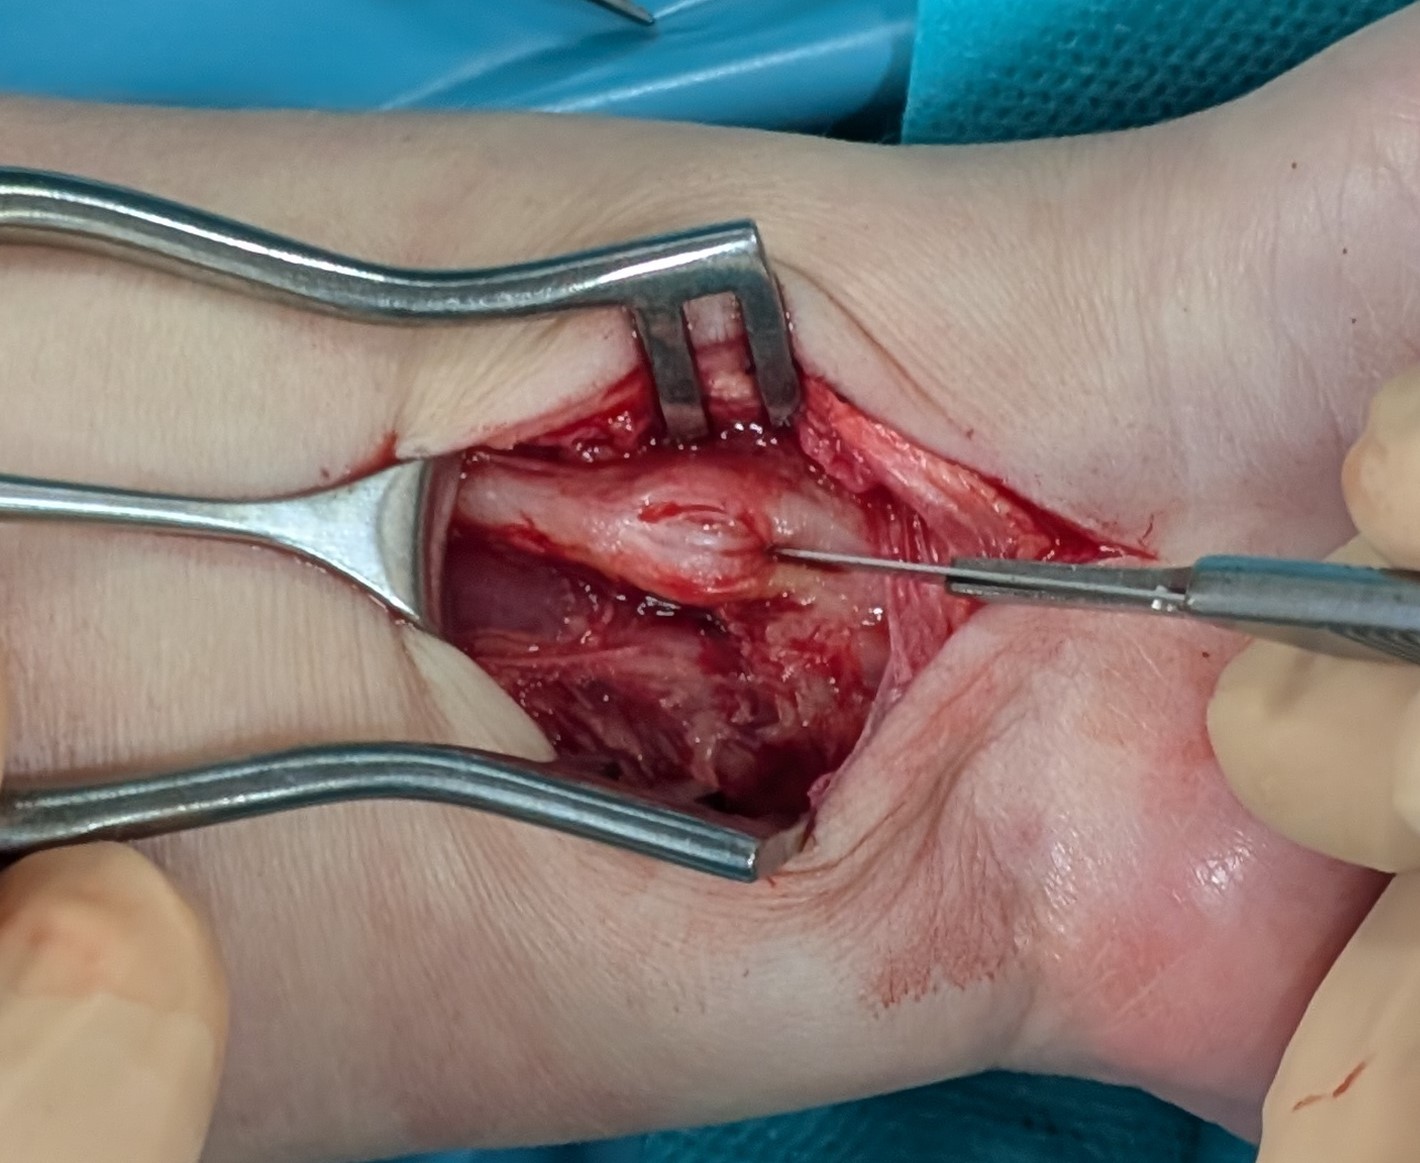

Enucleation of the median nerve tumour under WALANT: a case report

A case of a median nerve tumour (schwannoma) located in the distal part of the forearm, which was enucleated from the nerve under local anaesthesia (WALANT), without the use of a tourniquet on the arm to obtain a bloodless surgical field, is presented. To the best of the authors’ knowledge, this is the first described case of nerve tumour surgery under this anaesthesia. It shows that operation of nerve tumours can be performed under WALANT, without deteriorating of patients’ safety and surgeons comfort. The authors believe that presentation of this case can be interesting for hand surgeons and will encourage them to extend the scope of operations performed under WALANT.